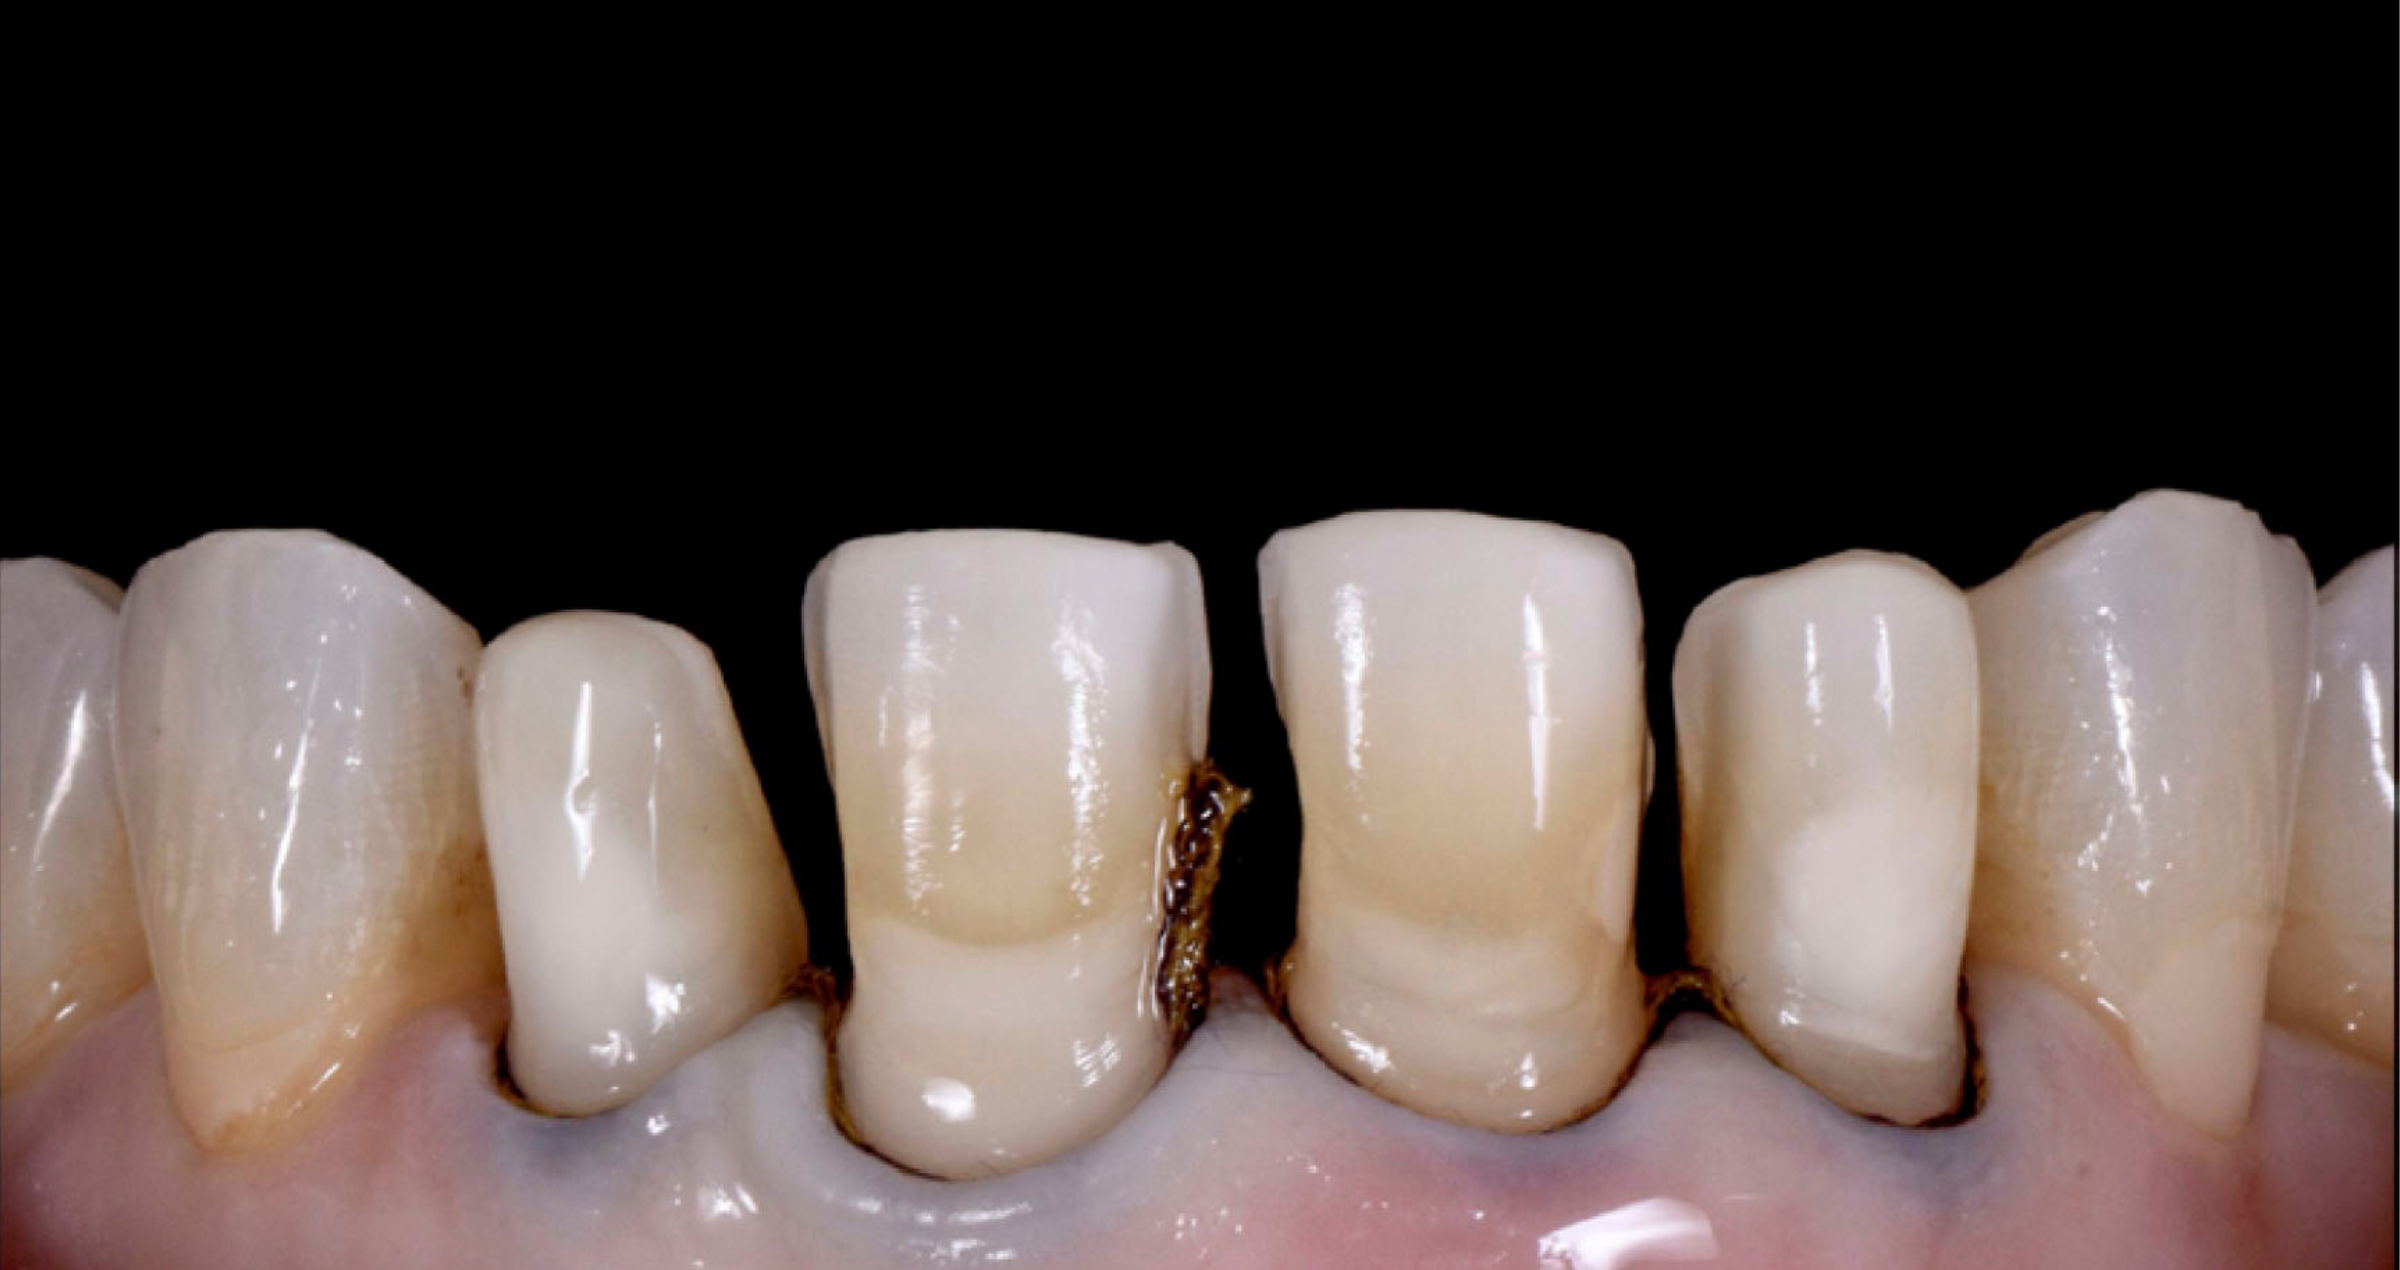

Fig. 2: Dettaglio delle preparazioni.